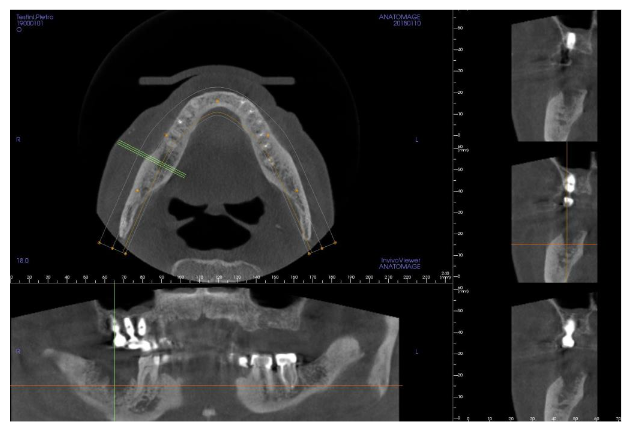

The lesion showed necrotic bone mixed with other parts in rapid growth: the cavity arrived so much deep that the lesion interested the lower alveolar nerve, causing a continuous, severe and burning pain interesting the mandible and radiated to the right ear, causing a worsening of the patient’s quality of life. Since his clinical conditions were very compromised above all for a severe heart failure it was decided to avoid any surgical approach, and the applied therapy was just a local disinfection and antibiotic drugs in case of infection. Moreover the patient used a lot of drugs (furosemide 125 mg twice a day, acetilsalicilic acid 100 mg once a day, Ivabradine 2.5 mg twice a day, Canrenone 50 mg a day, Silodosin 8 mg once a day and pantoprazole 40 mg once a day), and above all he used zolendronic acid (Zometa®) to control the bone metastasis growth derived from the prostatic cancer: this condition increased the risk to have a BRONJ as a postsurgical complication. However, for a continuous worsening of the symptoms and for the several infections of the mandibular lesion we decided, in agreement with his relatives, to surgically remove the gingival lesion cleaning the bone cavity with a conservative approach. To reduce the risk of postsurgical infections and of a bad healing (due to the zolendronic acid and the clinical conditions of the patients) we decided to fill the residual cavity with PRGF®-Endoret® autologous membranes, a particular platelet concentrate that improves and stimulates the healing processes inducing a good tissue regeneration. The Cone Beam Computer Tomography (CBCT) showed the extension of the bone lesion (images 3-4).